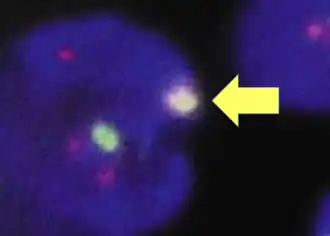

Fluorescence in situ hybridisation

FISH can be used to measure the number of copies of the gene which are present and is thought to be more reliable than immunohistochemistry.[47] It usually uses chromosome enumeration probe 17 (CEP17) to count the amount of chromosomes. Hence, the HER2/CEP17 ratio reflects any amplification of HER2 as compared to the number of chromosomes. The signals of 20 cells are usually counted.

Overlapping cells are also excluded from the count.

Overlapping cells are also excluded from the count. -

A yellow signal counts as one red and one green (which are overlapping)

A yellow signal counts as one red and one green (which are overlapping)